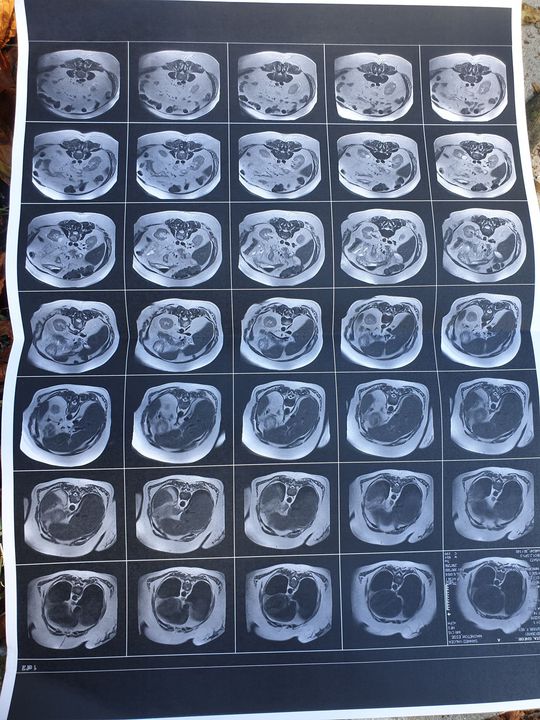

RMN abd

What is your diagnosis?